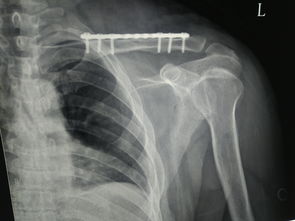

骨折在劇烈運動、交通事故等日常生活中經(jīng)常發(fā)生,很多家屬在患者骨折后都會迫不及待地給其大肆進補,以促進骨頭的生長和愈合,如濃濃的骨頭湯、大魚大肉以及鈣片等。這是飲食上的一個誤區(qū),骨折初期(1~2周)大多是制動期間,此時應(yīng)避免進食過于油膩的骨頭湯以及大量難以消化的肉類,也不宜攝入過高的鈣質(zhì),飲食只要易于消化和吸收即可,進補應(yīng)放到骨折的中、后期才能到調(diào)養(yǎng)的作用。

發(fā)生骨折時傷筋動骨,受傷部位因氣滯血瘀而腫脹,此時治療宜活血化瘀、行氣消散,飲食上以清淡為主,不能過早給予肥膩滋補之品,如骨頭湯、紅燒肉、帶皮雞湯等,否則不但容易增加胃腸道負(fù)擔(dān),造成消化不良、便秘,且使舊瘀不去而新骨難生,骨痂生長遲緩,導(dǎo)致影響日后關(guān)節(jié)功能的恢復(fù)。因此,在骨折早期,患者的飲食營養(yǎng)豐富而易于消化即可,可與一般人相同,避免進食油膩和辛辣品,多吃水果、蔬菜和粗纖維食物。如果有條件,可用三七10克,肉鴿1只,姜片適量、紅棗2個燉湯,肉鴿味道鮮美又不油膩,三七則有活血化瘀之效。

骨折2周后進入骨折的中后期,此時瘀腫已大部分被吸收,骨痂開始生長,病人經(jīng)過一段時間的臥床,機體處于高代謝狀態(tài),鉀、鈣等丟失較多,飲食上逐漸應(yīng)由清淡轉(zhuǎn)為適當(dāng)?shù)母郀I養(yǎng)補充,積極攝入維生素、鈣、鉀、鋅以及其他微量元素。此時,患者的食譜可以增加骨頭湯、三七煲雞、豬肝、牛奶、豆腐、蝦仁等富含鈣、蛋白質(zhì)的食物。滋補湯水以補益肝腎和氣血為主,以達到接骨續(xù)筋、促進骨痂生長加快的目的。推薦的食療方有豬骨當(dāng)歸枸杞湯,可用當(dāng)歸10克,骨碎補15克,枸杞10克,新鮮豬排250克,加3片姜片共煮2小時以上,飲湯吃肉。